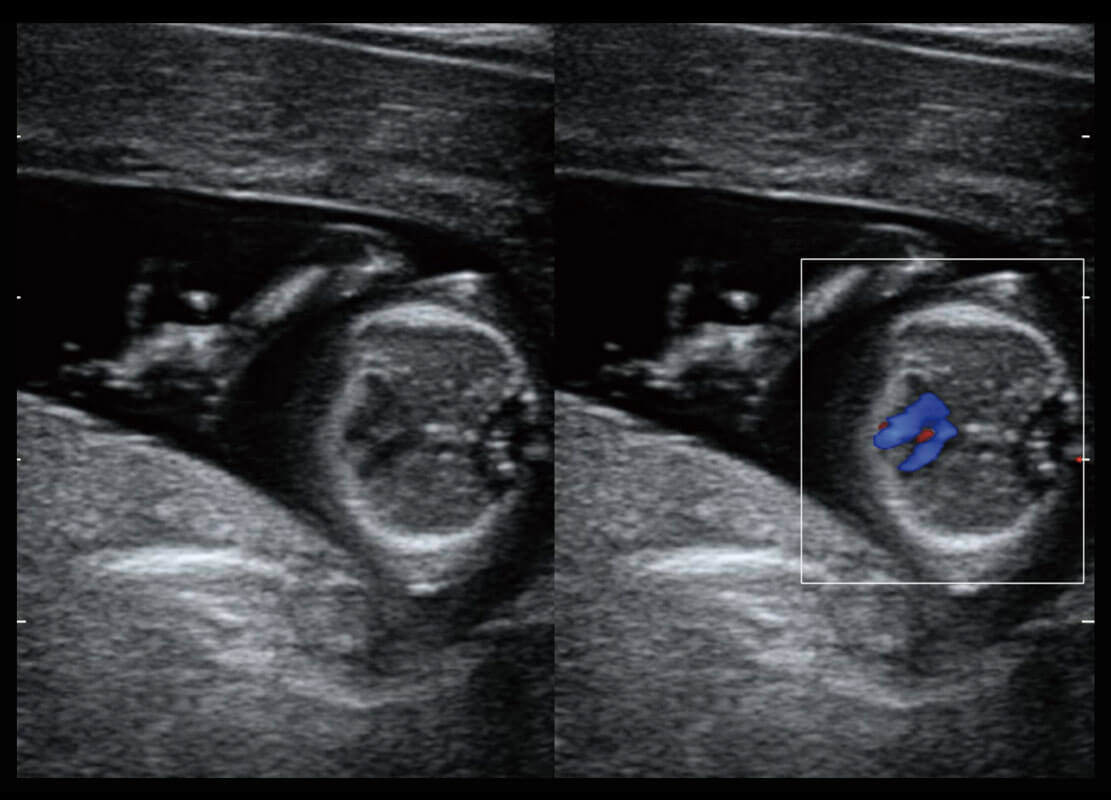

新生儿肝血管癌

新生儿脊髓圆锥

新生儿心脏

P60搭载宽频带线阵探头、宽景成像、弹性成像技术,为您提供乳腺应用方案。P60支持高频相控阵探头、线阵探头、腹部高频探头、腹部微凸探头等,丰富的探头群搭载敏感的彩色血流成像,适用于新生儿多种脏器检测要求,满足新生儿筛查需求。